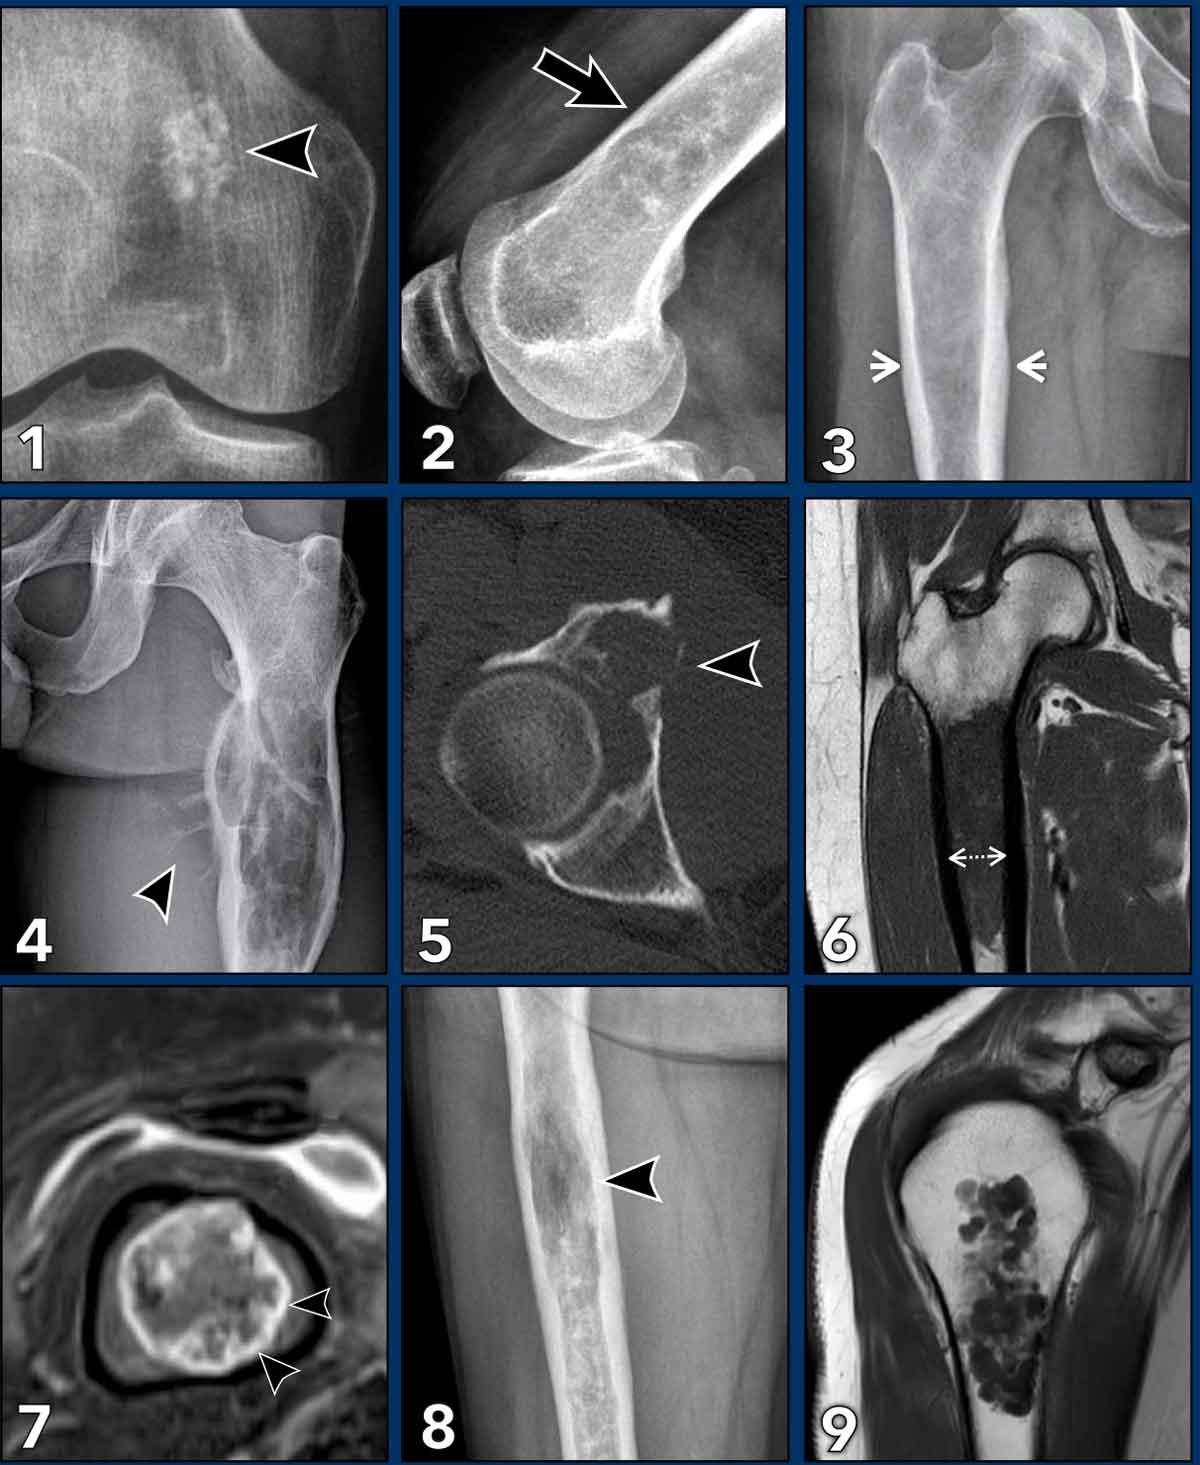

ACT versus high grade CS

Phân biệt giữa u sụn không điển hình (ACT) và u sụn sụn độ cao (CS độ cao) là nhiệm vụ quan trọng nhất của bác sĩ X quang, vì các khối u độ cao cần được cắt bỏ rộng rãi. Kể từ khi quan điểm điều trị thay đổi, ngày càng nhiều trung tâm điều trị ACT bằng phương pháp theo dõi thận trọng mà không phẫu thuật.

Cần tích cực tìm kiếm các đặc điểm như phù tủy xương quanh tổn thương, phản ứng màng xương, phá hủy vỏ xương và khối phần mềm để xác định khối u là CS độ cao. Giãn nở xương có thể gặp trong ACT nhưng phổ biến hơn trong CS độ cao.

Thành phần nhầy là dấu hiệu của độ ác tính cao hơn và cũng hiện diện trong các trường hợp như CS biệt hóa kém.

Ngấm thuốc tương phản động nhanh, xói mòn vỏ xương và vôi hóa chất nền có thể xuất hiện trong cả ACT lẫn CS độ cao, do đó các đặc điểm này không giúp phân biệt hai loại.

Kích thước có vai trò nhất định nhưng không phải là đặc điểm chính để phân biệt ACT với CS độ cao.

Trong trường hợp gãy xương bệnh lý trên nền ACT, có thể xuất hiện phù nề xung quanh và viêm màng xương. Luôn đối chiếu hình ảnh với tiền sử chấn thương lâm sàng và khuyến nghị chụp MRI theo dõi sau 3-6 tháng để đảm bảo các dấu hiệu này được giải quyết.

Chúng tôi sẽ trình bày một số trường hợp, trong đó bạn cần phân biệt giữa u sụn không điển hình (ACT) và sarcôm sụn.

Trường hợp lâm sàng

Hãy quan sát các hình ảnh và xác định xem bạn đang đối mặt với một ACT hay CS.

Sau đó tiếp tục đọc.

Hình ảnh

Có một tổn thương đo được hơn 20 cm ở thân xương đùi.

Lưu ý các vôi hóa dạng bỏng ngô trong nền tổn thương.

Có một nốt khu trú (trong vòng tròn màu vàng) gây xói mòn vỏ xương và có sự mở rộng nhẹ của ống tủy xương.

Hình ảnh MR cho thấy mô mỡ xen kẽ giữa các nốt sụn.

Có tín hiệu cao trên ảnh T1W mặt phẳng đứng dọc và tín hiệu thấp trên ảnh xóa mỡ (các mũi tên).

Có một nốt khu trú gây lõm vỏ xương (<10%) và có sự mở rộng nhẹ của ống tủy xương.

Kết luận

Tổn thương được chẩn đoán là ACT và vẫn ổn định trong quá trình theo dõi.

Ca bệnh

Trước tiên hãy quan sát các hình ảnh và quyết định xem bạn đang xử lý với ACT hay CS.

Có một tổn thương tiêu xương được xác định rõ >10 cm ở thân xương đùi đoạn gần với vôi hóa chất nền sụn dạng bỏng ngô.

Có sự giãn nở của xương, tuy nhiên không có dấu hiệu xói mòn vỏ xương rõ ràng hay phản ứng màng xương.

Dựa trên hình ảnh X-quang đơn thuần, khối u này có thể là một ACT hoặc sarcoma sụn độ cao hơn. Bước tiếp theo là thực hiện MRI để đánh giá đặc điểm chi tiết hơn.

MRI xác nhận bản chất sụn của khối u với các nốt sụn tăng tín hiệu trên T2 DIXON cho thấy ngấm thuốc kiểu vách-nốt sau tiêm thuốc tương phản.

Tuy nhiên, cũng có phù tủy xương đáng kể ở phía gần (mũi tên đen) và phản ứng màng xương kèm ngấm thuốc (mũi tên trắng).

Các đặc điểm này rất đáng ngờ cho chẩn đoán u sụn ác tính độ cao.

Hình ảnh T1 axial xác nhận tình trạng lõm vỏ xương phía trước sâu chiếm khoảng 1/3 vỏ xương, tức là lõm vỏ xương mức độ rộng (> 10% chu vi khối u).

Cắt bỏ đầu trên xương đùi đã được thực hiện.

Chẩn đoán cuối cùng: sarcoma sụn độ II

Phim X-quang cho thấy các vùng nhỏ có vôi hóa chất nền sụn.

Hình ảnh T2W FS mặt phẳng vành tai minh họa kích thước tổn thương bị đánh giá thấp hơn so với phim thường.

Lưu ý các nốt sụn tăng tín hiệu kết hợp với các vùng tín hiệu thấp tương ứng với hình ảnh vôi hóa trên X-quang.

Sau tiêm thuốc tương phản, thấy kiểu ngấm thuốc điển hình dạng vòng và cung.

Do kích thước 5,7 cm và mức độ lan đến vỏ não, tổn thương này được gọi là ACT và sẽ được theo dõi bằng MRI.

Phim X-quang cho thấy tổn thương tiêu xương dạng đa ổ, có tính chất giãn rộng tại vùng hành xương đầu gần xương quay.

Có thể thấy một số chấm vôi hóa nhỏ bên trong tổn thương.

Khối u tăng tín hiệu trên chuỗi xung T2 DIXON và có các vùng phá hủy vỏ xương.

Sau tiêm thuốc cản quang, xuất hiện hình ảnh ngấm thuốc điển hình dạng vách-nốt và các vùng chất nhầy không ngấm thuốc, cũng hiện diện trong thành phần phần mềm.

Xung quanh khối u có hình ảnh phù nề phần mềm.

Những đặc điểm này giúp chúng ta đưa ra chẩn đoán u sụn ác tính độ cao (chondrosarcoma độ cao).

Kết quả giải phẫu bệnh sau cắt rộng cho thấy sarcoma sụn độ II.